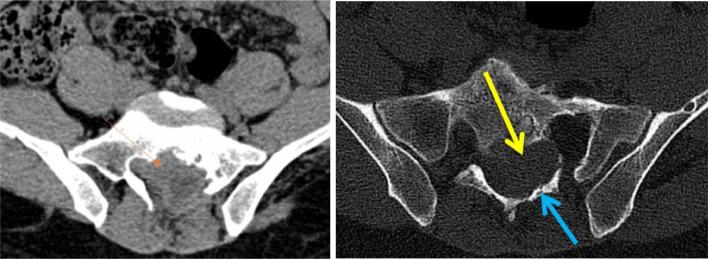

原发性脊椎-髓内及硬膜外包虫病导致髓质受压的罕见病因影像学表现:影像学的作用

Iconographies of rare causes of medullary compression due to primary vertebro-medullary and epidural hydatidosis: Contribution of imaging.

Vertebro-medullary and epidural hydatidosis are a very rare entity, representing 2% of all locations, and is even rarer when it involves a solitary location. It is often asymptomatic. The diagnosis is usually made during complications, particularly medullary compression or extension to the costal cage, which represents a therapeutic emergency. Surgical treatment must be radical to prevent recurrences. We report 2 cases: the first case was a 61-year-old female involved costo-vertebral hydatidosis, and the second was an 18-year-old man with primary sacral epidural location. The objective of our report is to add these 2 atypical locations of hydatid cysts to the existing literature and to present their radiological images to aid radiologists in diagnosis.

摘要

脊椎-髓内和硬膜外包虫病是一种非常罕见的疾病,占所有发病部位的2%,当它累及单一部位时更为罕见。它通常无症状。诊断通常在出现并发症时做出,特别是髓内压迫或向胸廓扩展,这是一种治疗急症。手术治疗必须彻底以防止复发。我们报告2例:第一例是一名61岁女性,患有肋-椎包虫病,第二例是一名18岁男性,原发性骶部硬膜外发病。我们报告的目的是将这2个包虫囊肿的非典型发病部位补充到现有文献中,并展示其放射影像以帮助放射科医生进行诊断。